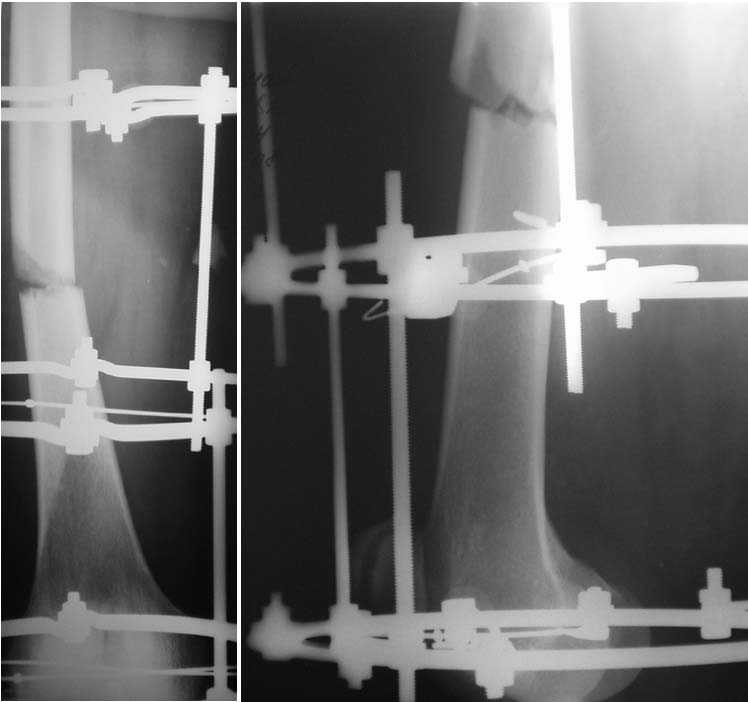

Мужчина, 44 г. Травма в ДТП 22.08.08: открытый перелом ср\3 диафиза правой бедренной кости, закрытый оскольчатый перелом правого локтевого отростка со смещением, в\3 правой лучевой кости со смещением, закрытый перелом верхушки внутренней лодыжки правой голени.

Находился на лечении в одной из городских больниц (где в ургентном порядке произведена операция - ПХО ран, ЧКО правого бедра аппаратом спице-стержневого типа, иммобилизация правого предплечья гипсовой повязкой). Переведен для дальнейшего лечения в ДНИИТО. Через 18 дней после травмы выполнены рентгенограммы таза - диагностирован перелом шейки бедра. На данный момент раны бедра заживают вторично с участками некроза.

Male, 44 y.o. Trauma in MVA 22.08.08: open fracture of right femur (middle shaft), close fractures of right elbow and pilon.

He was in rural hospital were debridgement and Ilizarov frame for femur were performed. Now, he is in Regional Trauma Hospital. After 18 days of trauma x-ray of pelvis were performed – fracture of right femur neck. Wounds at femur is healing with small points of necrosis.

Hi looking at pictures i thimk that the ilizarov frame can give union at the fracture site in shaft may be with compression /+/- bone grafting .we have two options

1. continue with frame and do a cannulatted cancellous screw fixation for femur neck .

2. if ur soft tissue condition allows removel of frame and reconst nailing with supllementar bone grafting at both fracture site. muscle pedicle bone graft at neck.

Самое предсказуемое вмешательство было бы - закрытая репозиция шейки и фиксация спонгиозными винтами. А потом диафиз ретроградно заштифтовать

(сейчас или когда-то позже).

Absolutely, if wound is doing fine, I will perform a IM Rod in reconstruction mode for diaphysis and cervical neck fracture.

If not, I will do Cannulated screw for cervical neck fracture and keep the Ex Fix Frame.

Hi! In this case we can see complecated fracture femoral neck, I think subcapital with comminution to midcervical area.About fracture shaft femur this very easy- intramedullary interlokking nail

Ilizarov external fixation beutifull solution but is more damanded than rod .

For this case may be use Reconstraction Nail - TEN that posible fixation fracture neck and shaft

Becouse very complecated case may be need open reduction of neck fracture. Very critically to explain to patient about very higt percent AVN femoral head in this type fracture.